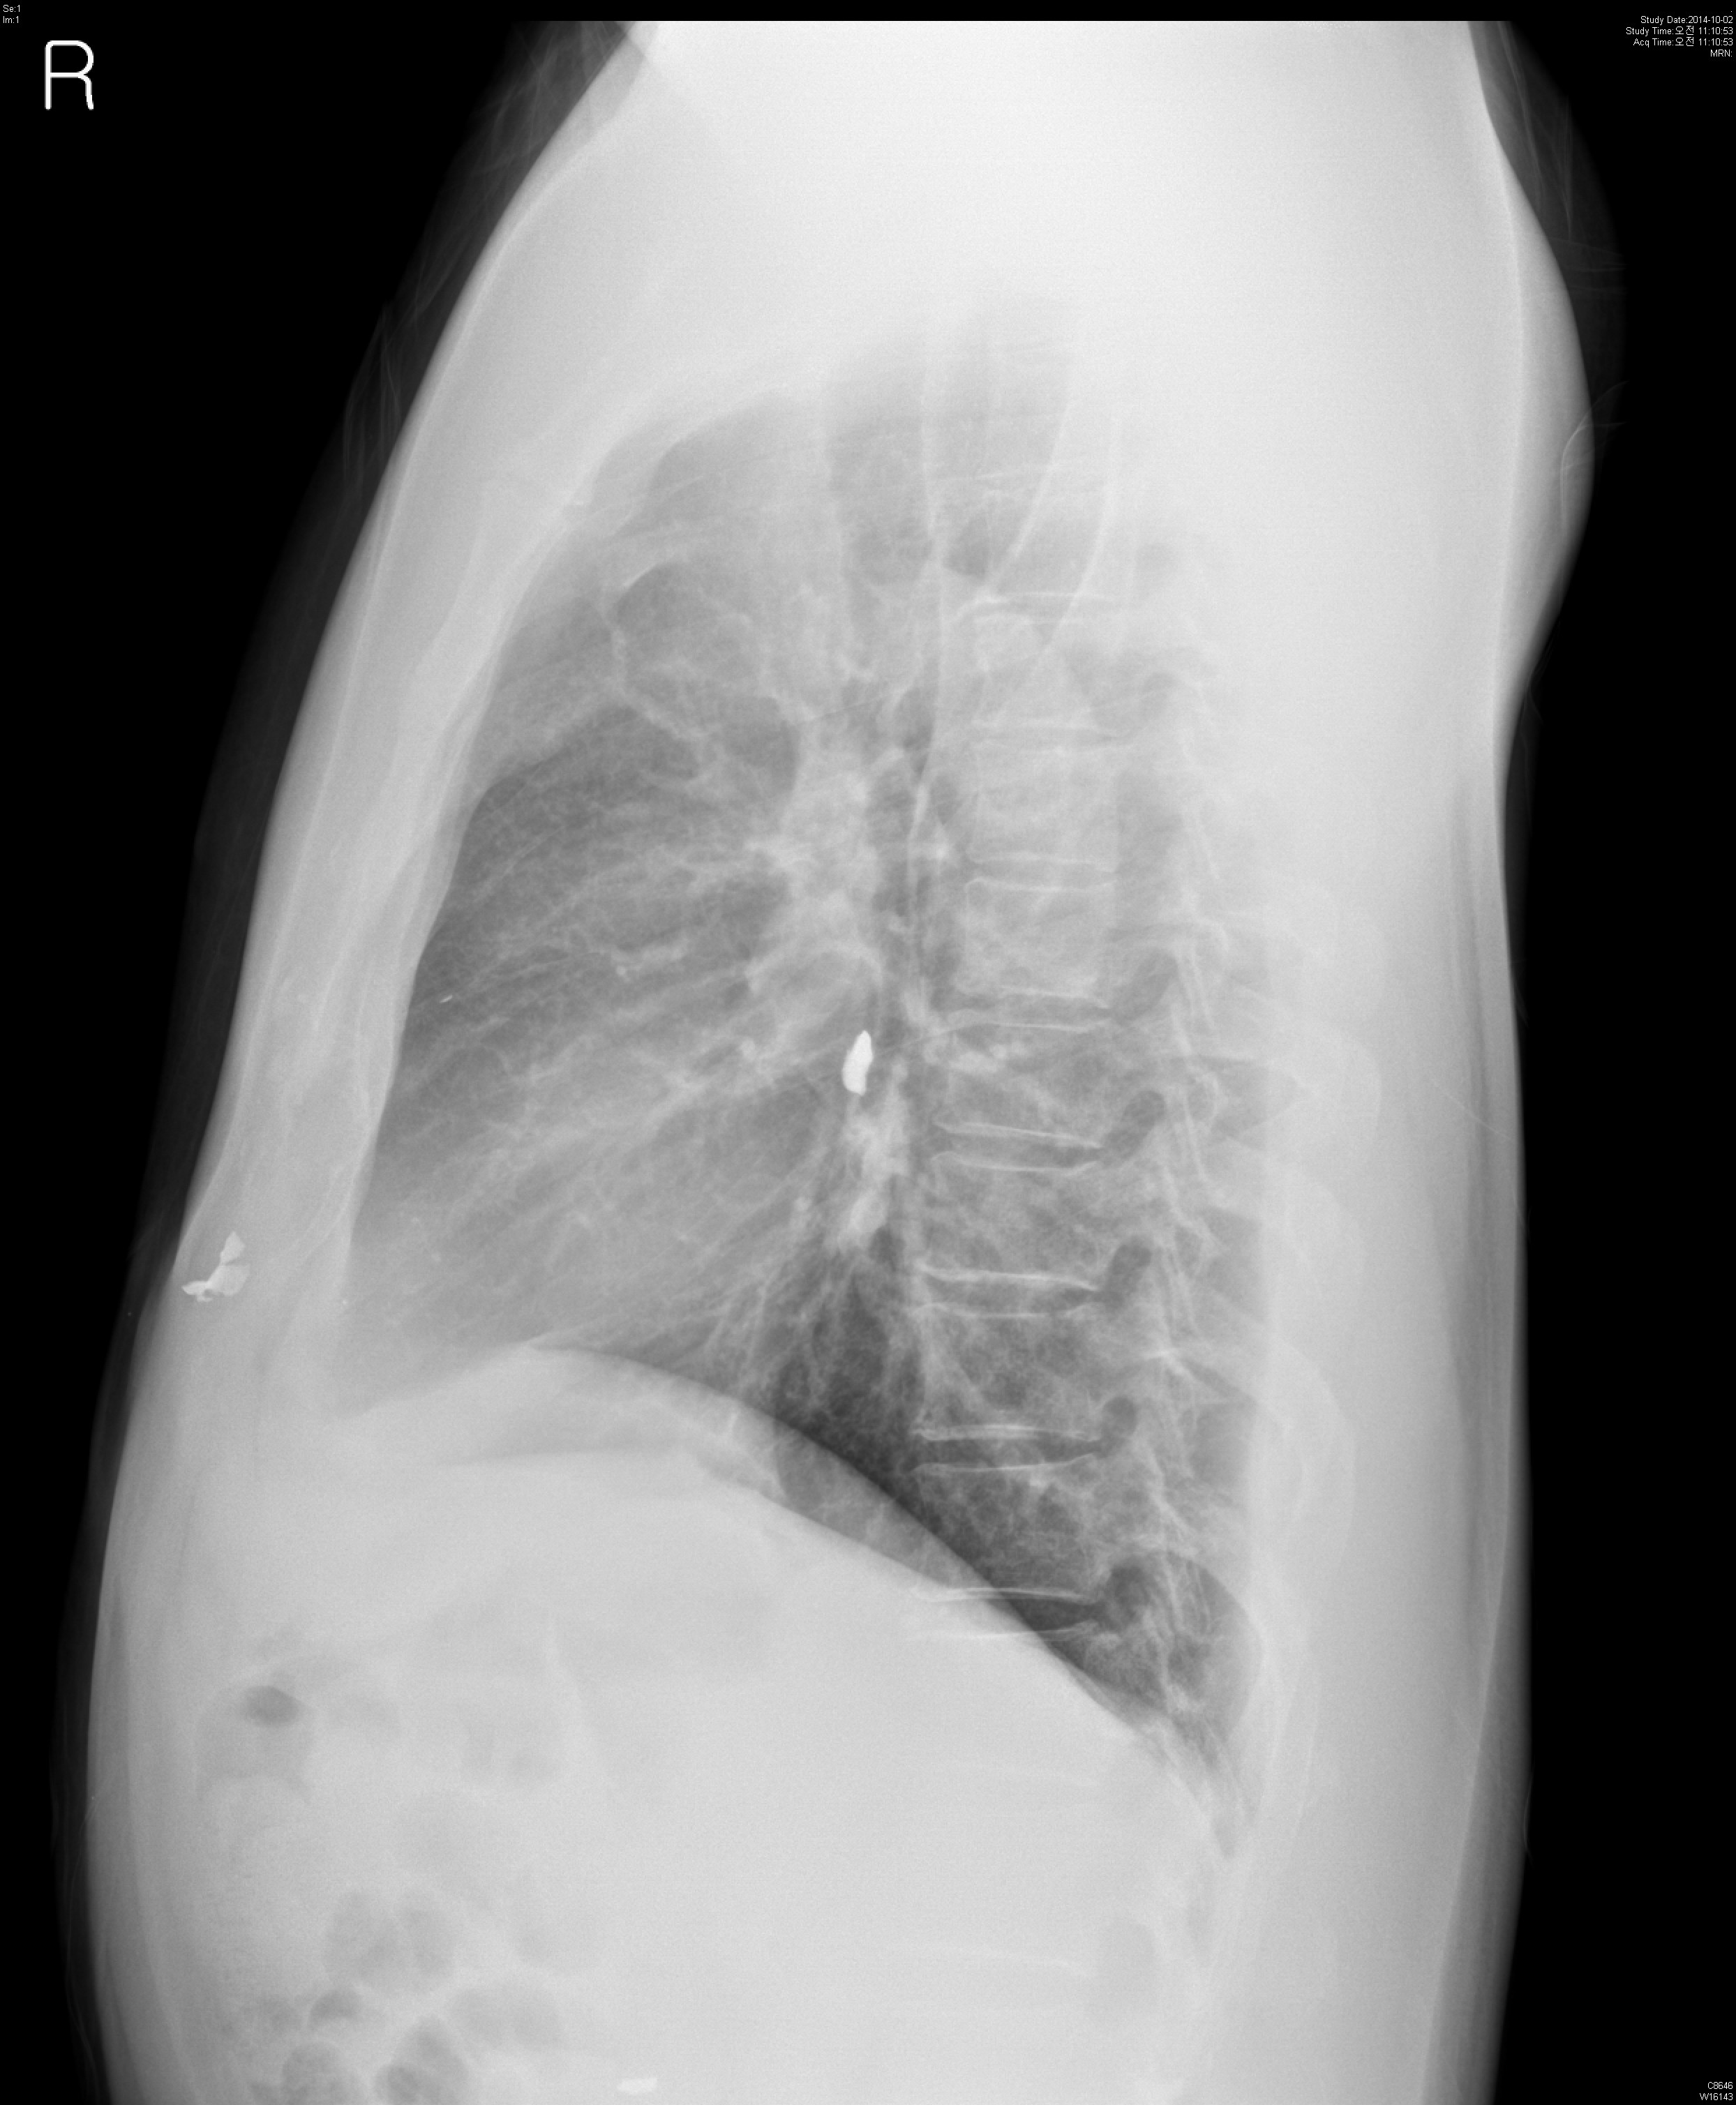

M/54, Abnormal CXR on Operability consult

¾È°ú¿¡¼­ ¼ö¼ú °èȹ Áß Chest PA »ó¿¡¼­ ¹ß°ßµÈ calcification À¸·Î ½ÃÇàÇÑ Chest CT ÀÔ´Ï´Ù.

È£Èí±â Áõ»óÀº ¾ø¾úÀ¸¸ç, ÀÌÀü ±º´ë¿¡¼­ ÆøÅºÀ» ¸ÂÀº °ú°Å·ÂÀÌ ÀÖ½À´Ï´Ù.